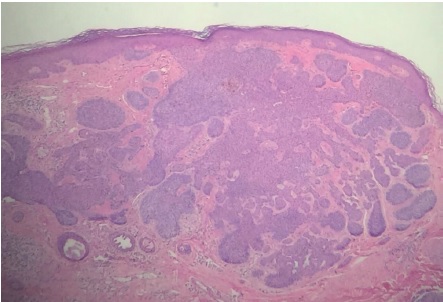

Paciente do sexo feminino, 65 anos, parda, queixando-se de prurido no couro cabeludo há um mês. Ao exame observava-se na região occipital: placa verrucosa, discretamente eritematosa medindo cerca de 2,5cm no seu maior eixo (Figuras 1 e 2). Segundo a paciente, desde o nascimento apresentava lesão assintomática no couro cabeludo que, há um mês, tornara-se pruriginosa. Optou-se por biópsia incisional da lesão e exame histopatológico, o qual evidenciou carcinoma basocelular nodular (Figura 3). Realizada então a excisão completa da lesão com margem, cujo exame histopatológico revelou: nevo sebáceo associado a siringocistoadenoma papilífero, adenoma tubular apócrino, triquilemoma (Figuras 4 a 7) e fibrose dérmica cicatricial.

O NSJ, conhecido também como nevo organoide, é mais incidente no couro cabeludo, podendo apresentar-se na face e menos comumente nos membros.3,5 Ocorre em aproximadamente 0,3% dos indivíduos, sem predileção por gênero. A lesão em geral está presente ao nascimento e apresenta-se como placa bem delimitada constituída por múltiplas pápulas confluentes de coloração amarelo-alaranjada ou amarelo-acastanhada, predominantemente no couro cabeludo, onde cursa com alopecia no local da lesão.3 Apresenta distribuição bimodal: durante a puberdade, quando sua superfície torna-se espessada e verrucosa por estímulos hormonais aos componentes écrinos e apócrinos, podendo, na fase adulta, a lesão se tornar nodular com a ocorrência de ulcerações e crostas. A possibilidade de surgimento de neoplasias secundárias nessa fase varia de dez a 30%, sendo as principais o carcinoma basocelular, o siringocistoadenoma papilífero (ambos observados nessa paciente) e o tricoblastoma.3